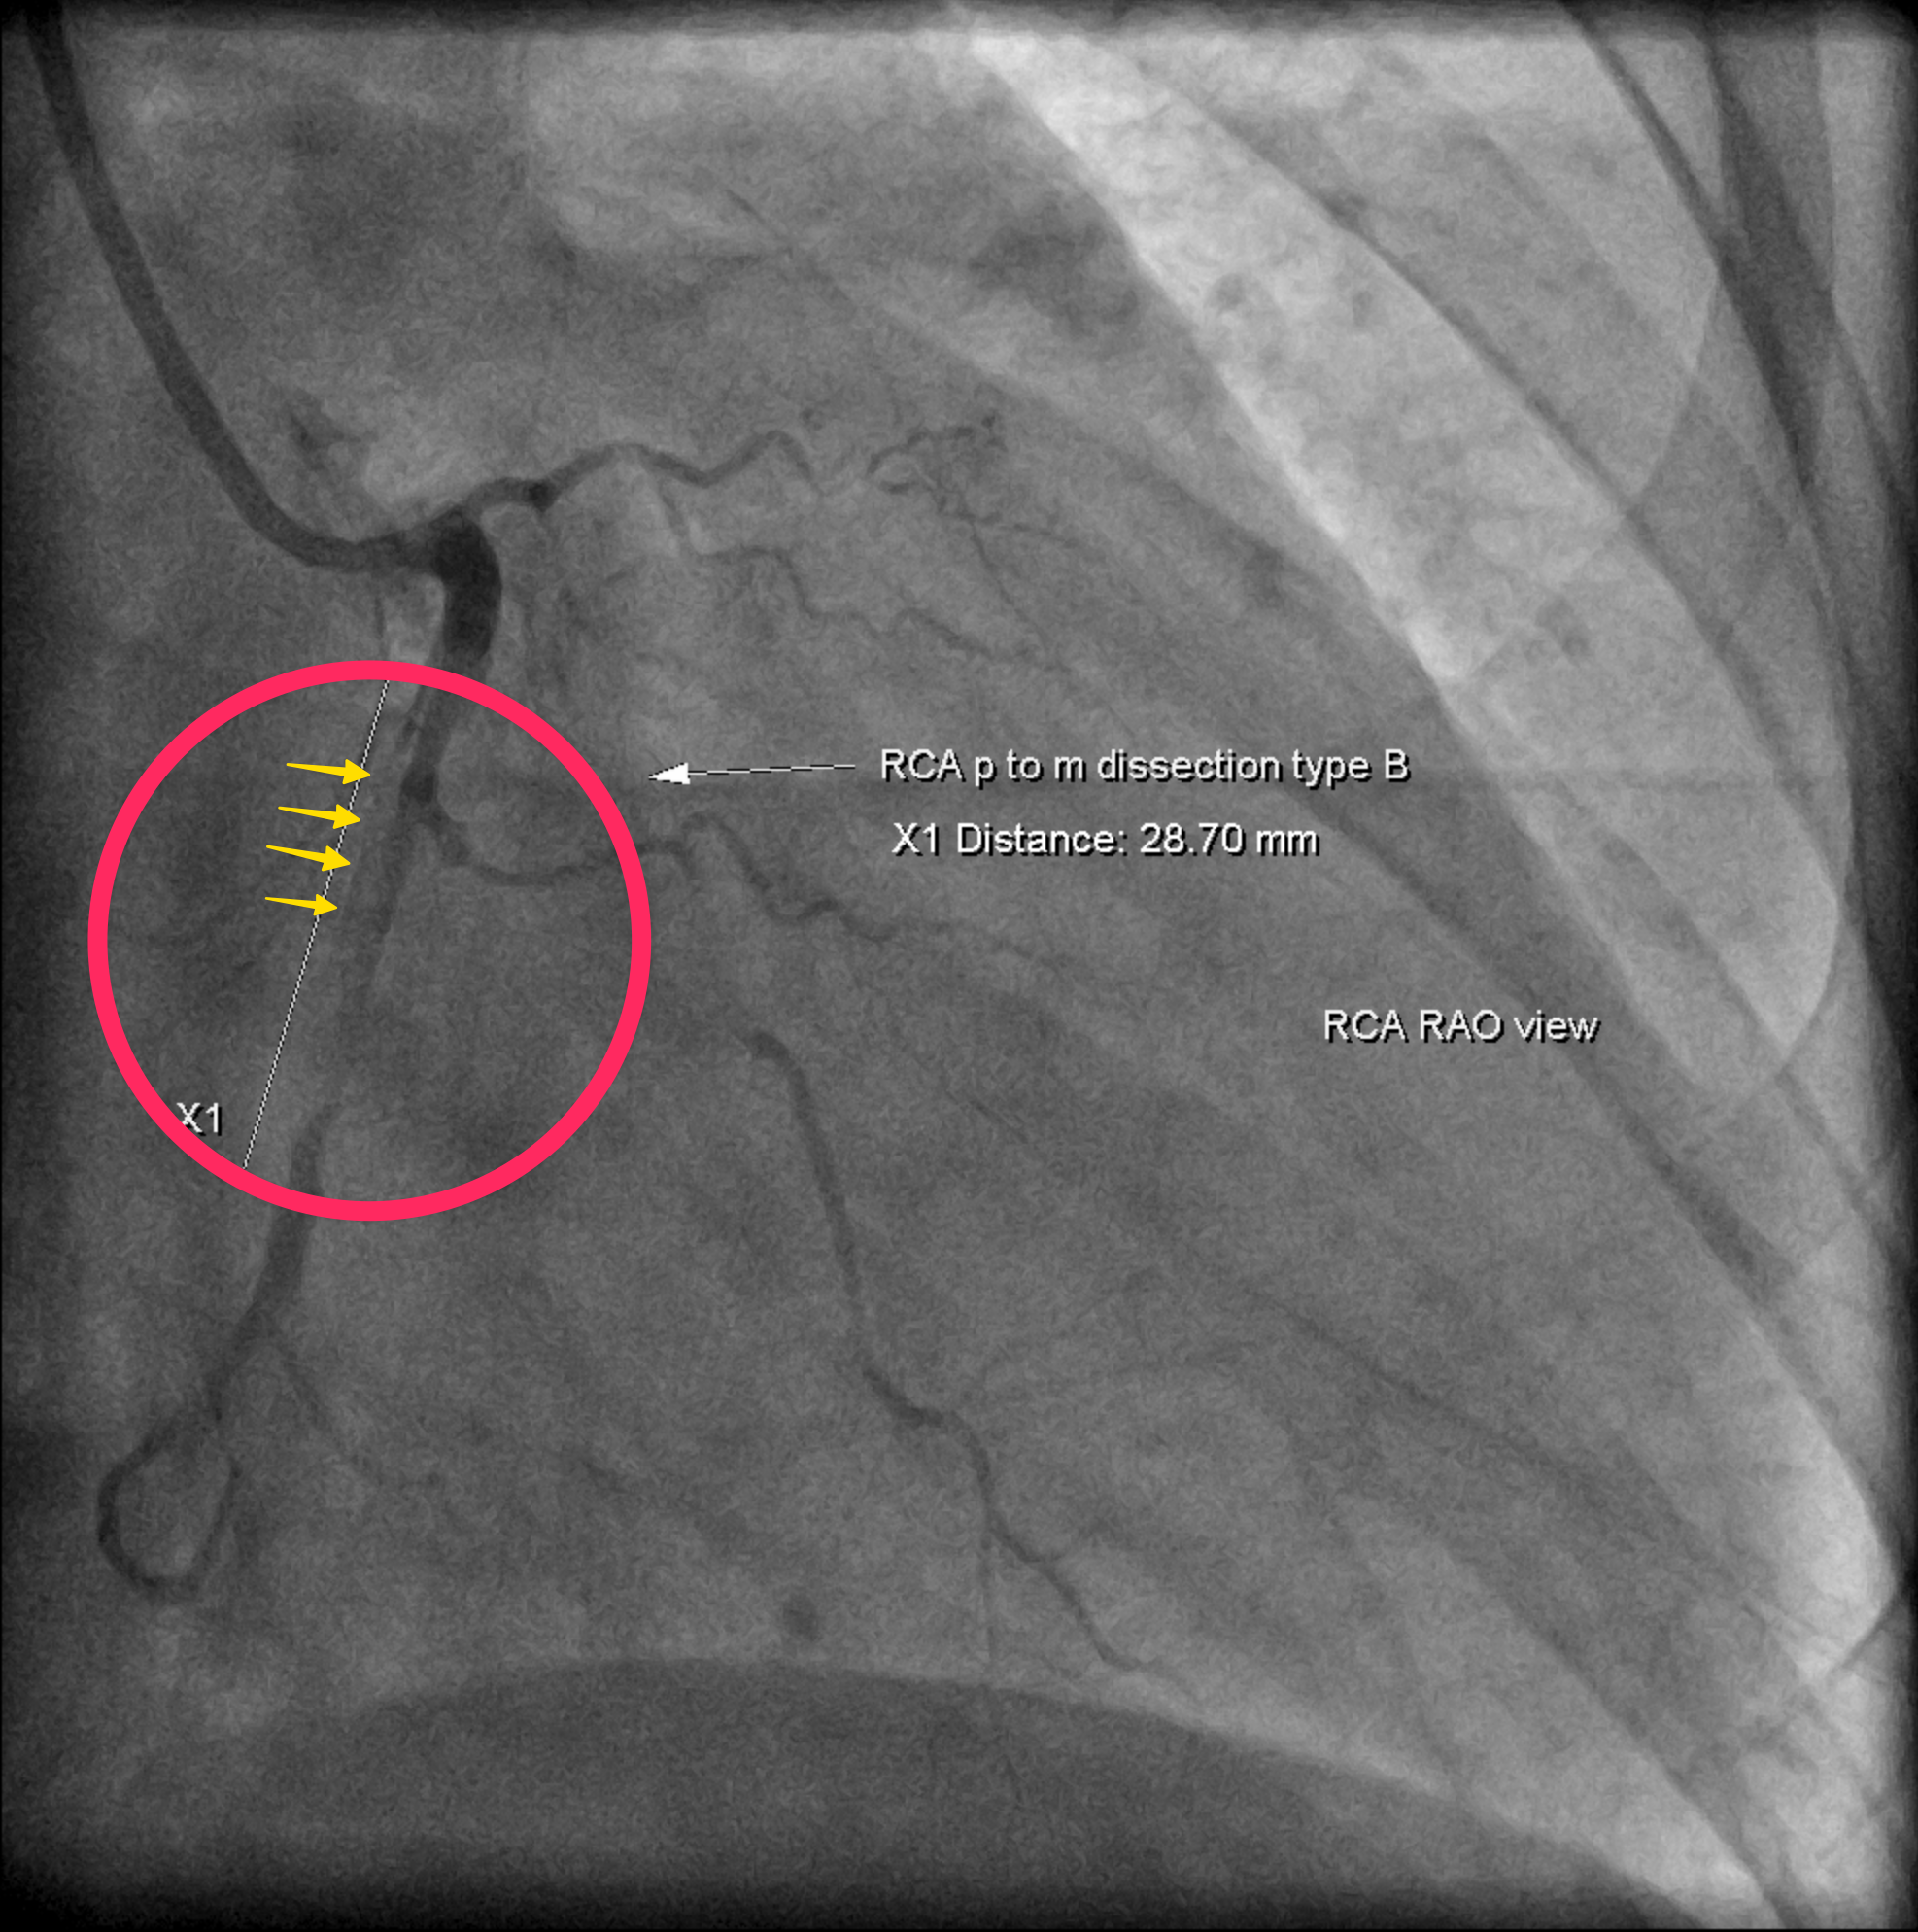

我們的這個案例(Fig.6),也可以見到在RCA有很長一段的血管突然變狹窄。

紅色圈圈是很長一段血管突然狹窄區塊(intramural hematoma壓迫血管的地方)

黃色箭頭隱約可見原本血管壁管腔的位置